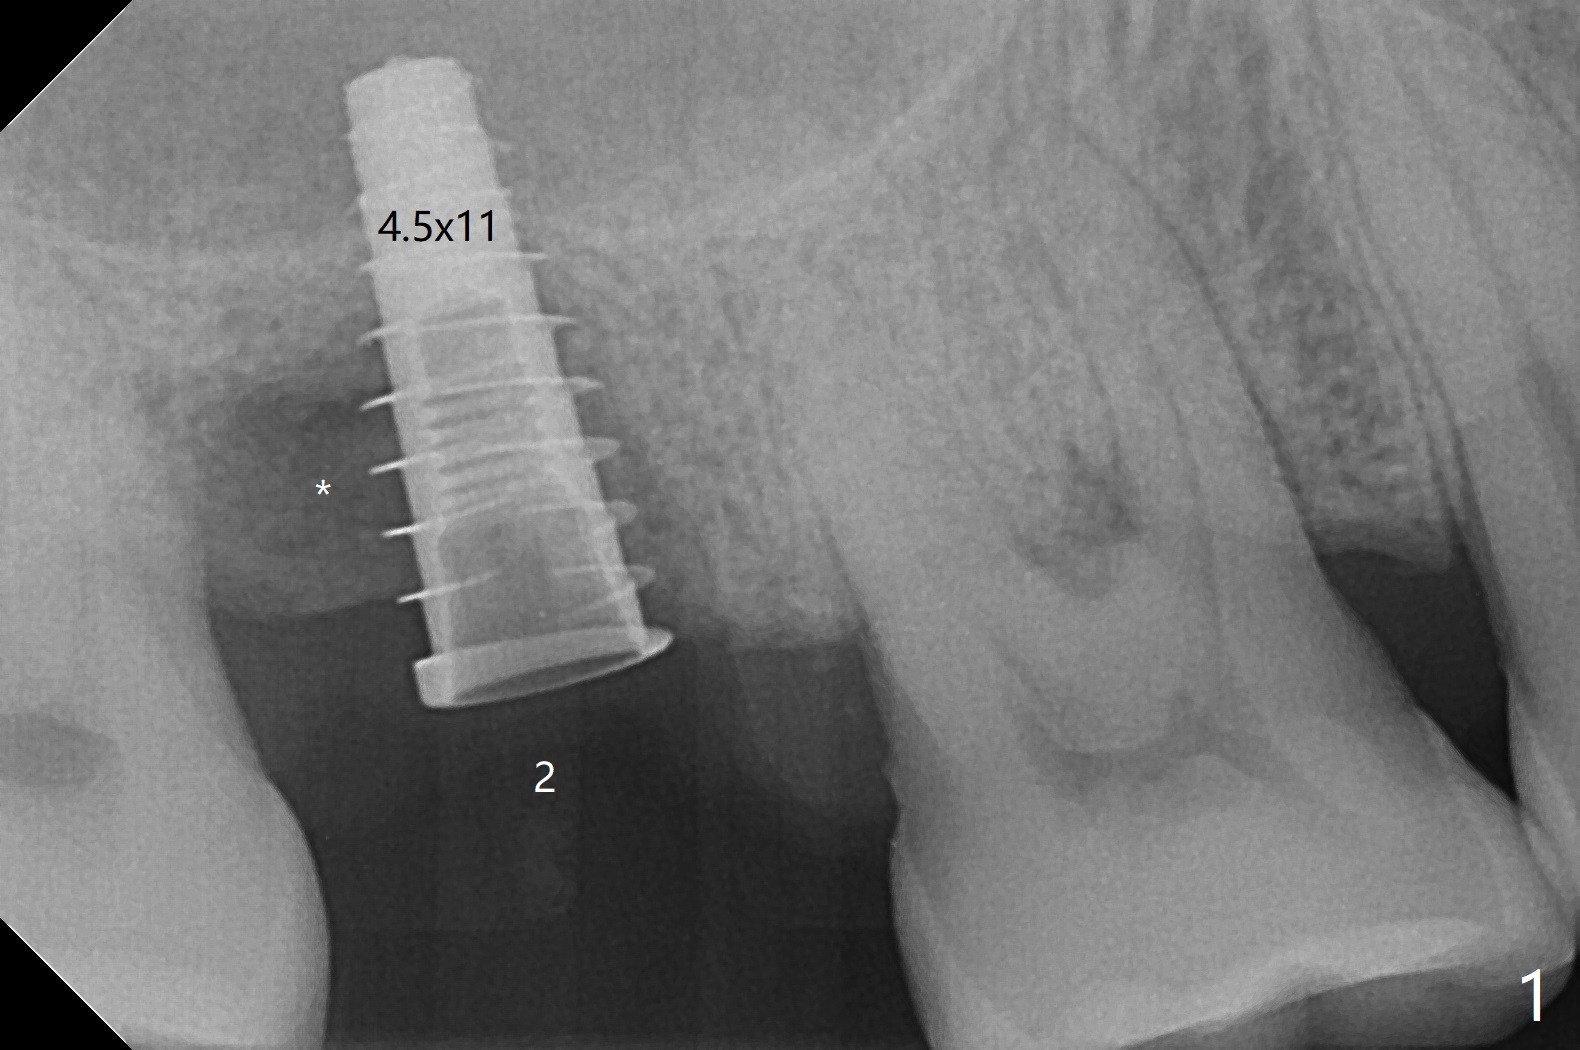

The tooth #2 has severe distobucal (DB) infection before and after extraction (Fig.1 *); sinus lift is done with 4.5x11 mm dummy implant using guide. After placing bone graft into the sinus and the osteotomy (Fig.2 black *), a 5x9 mm implant is placed with >30 Ncm. Second round of bone graft is placed around the implant, including DB defect (white *). Then a 5x4(2) mm pair abutment is placed, followed by the third round of bone graft (Fig.3 *). Finally an immediate provisional is fabricated to keep the graft in place. The implant is loose nearly 4 months postop.